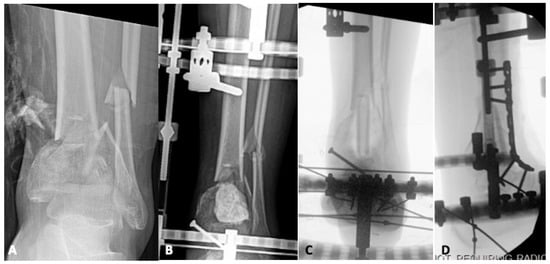

4.1. Infection

4.2. Bone Defects